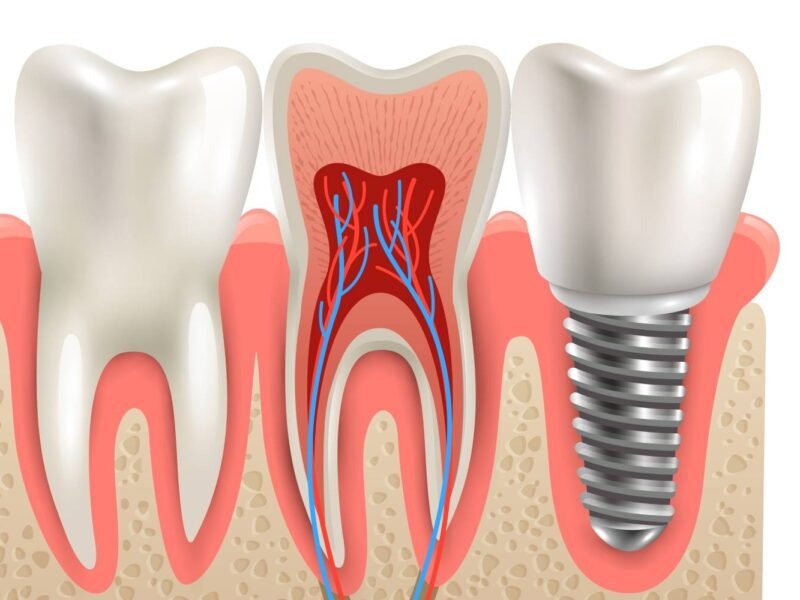

Root canal Treatment

Save your natural tooth and relieve pain with advanced Root Canal Treatment at Dr. Navin Dental and Aesthetics Clinic. Our skilled dental specialists use the latest technology and painless techniques to treat infected or damaged teeth effectively restoring both comfort and function.

What Is a Root Canal Treatment?

A Root Canal Treatment (RCT) is a dental procedure used to remove infection or inflammation from inside a tooth. The process involves cleaning the infected pulp (the soft tissue inside the tooth), disinfecting the root canals, and sealing them with a biocompatible material to prevent future infections.

This treatment helps save your natural tooth, eliminating the need for extraction and maintaining your smile’s natural appearance.

Our RCT Procedure

Diagnosis & Digital X-rays: We identify the source of infection using advanced imaging.

Local Anaesthesia: Ensures a completely painless experience.

Cleaning & Disinfection: The infected pulp is removed, and the canal is cleaned thoroughly.

Filling & Sealing: The canals are sealed to prevent reinfection.

Crown Placement: A dental crown is placed to protect and strengthen the treated tooth.